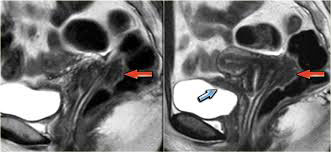

• MRI Scan: Provides enhanced visualization in cases of deep infiltrating endometriosis affecting the bowel, bladder, or ligaments.